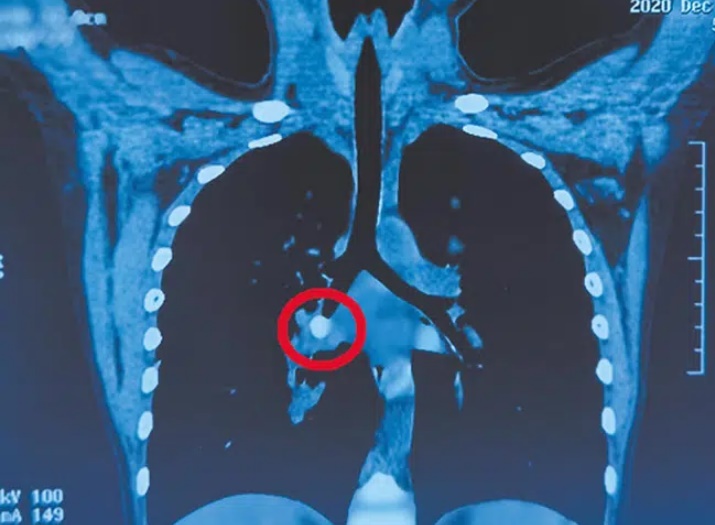

Chụp CT phổi cho thấy có bóng dị vật mật độ cao ở vùng dưới phổi phải của trẻ, làm tắc phế quản. Căn cứ vào bệnh sử, bác sĩ nghi ngờ dị vật chính là chiếc răng cửa mà cháu bé đã bị rụng cách đây 5 ngày. Những ngày qua, bệnh nhi trong tình trạng thiếu oxy, chỉ có phổi trái mới thực sự "hoạt động", nên cần phải loại bỏ dị vật càng sớm càng tốt. Đêm đó, bác sĩ Lâm Gia Huệ và bác sĩ Châu Trường Lộ từ Khoa Tai Mũi Họng của bệnh viện đã tiến hành phẫu thuật cho đứa trẻ.

Hình ảnh chiếc răng mắc kẹt trong phế quản bé.